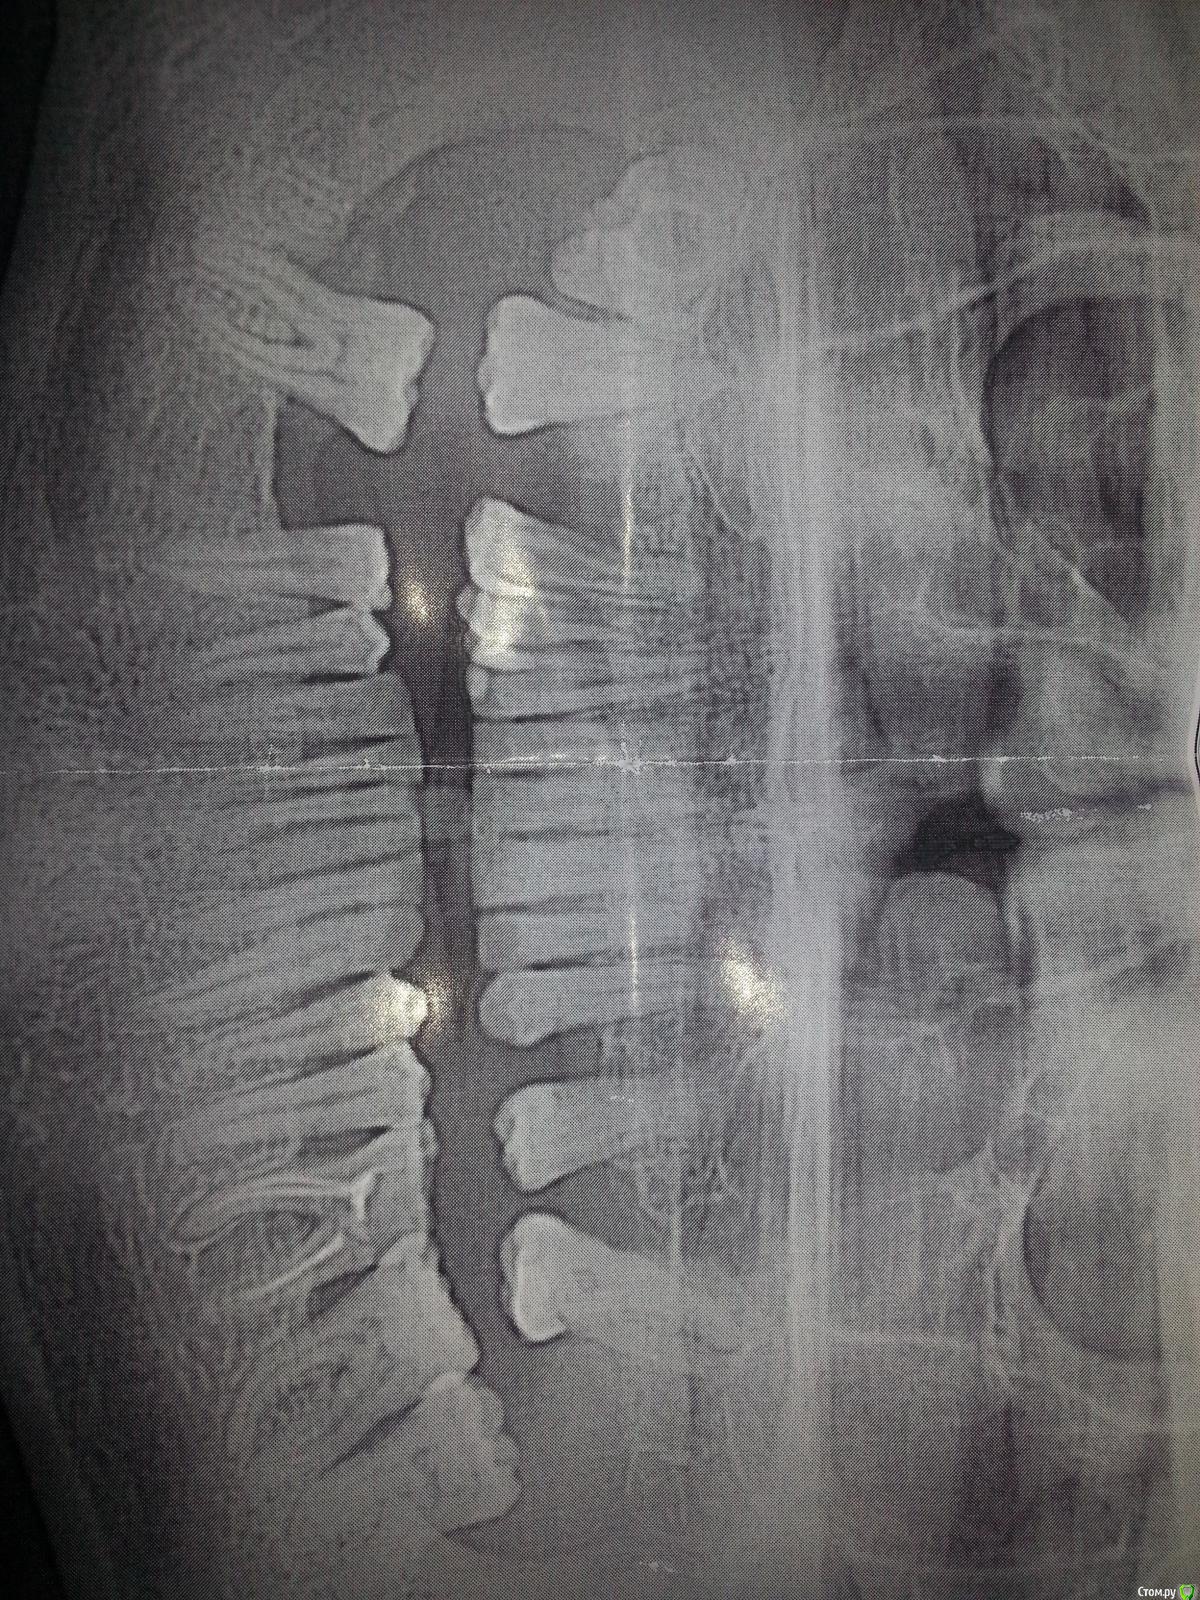

АнтонТЛТ Опубликовано 24 ноября, 2015 Поделиться Опубликовано 24 ноября, 2015 (изменено) http://i66.fastpic.ru/big/2015/1124/66/c5309b8db5b8065ca96aefca08680e66.jpgП.с. это 48 Изменено 24 ноября, 2015 пользователем АнтонТЛТ 11 Ссылка на комментарий

Карен Аванесов Опубликовано 24 ноября, 2015 Поделиться Опубликовано 24 ноября, 2015 внезапно 9 Ссылка на комментарий

an_ver Опубликовано 24 ноября, 2015 Поделиться Опубликовано 24 ноября, 2015 внезапноМногоножка)) Ссылка на комментарий

Карен Аванесов Опубликовано 24 ноября, 2015 Поделиться Опубликовано 24 ноября, 2015 не смотря на многоногость 20 минут.... Ссылка на комментарий